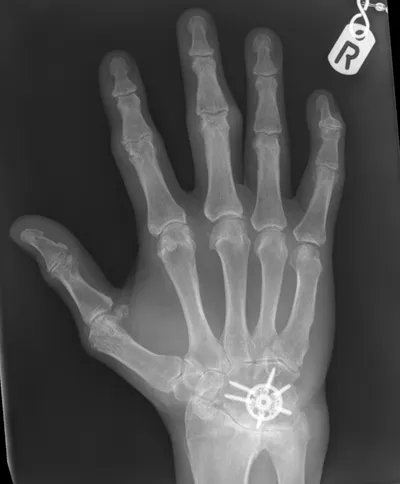

This collection contains 1 radiology images related to metalwork, including various imaging modalities such as X-rays, MRIs, CT scans, and ultrasound images commonly used in medical diagnosis and education.